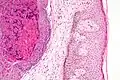

Histologically, molluscum contagiosum is characterized by molluscum bodies (also known as Henderson-Patterson bodies) in the epidermis, above the stratum basale, which consist of cells with abundant large granular eosinophilic cytoplasmic inclusion bodies (accumulated virions) and a small nucleus that has been pushed to the periphery.[19][20]

Low magnification micrograph of a molluscum contagiosum lesion

Low magnification micrograph of a molluscum contagiosum lesion -

Low-magnification micrograph of molluscum contagiosum, H&E stain

Low-magnification micrograph of molluscum contagiosum, H&E stain -